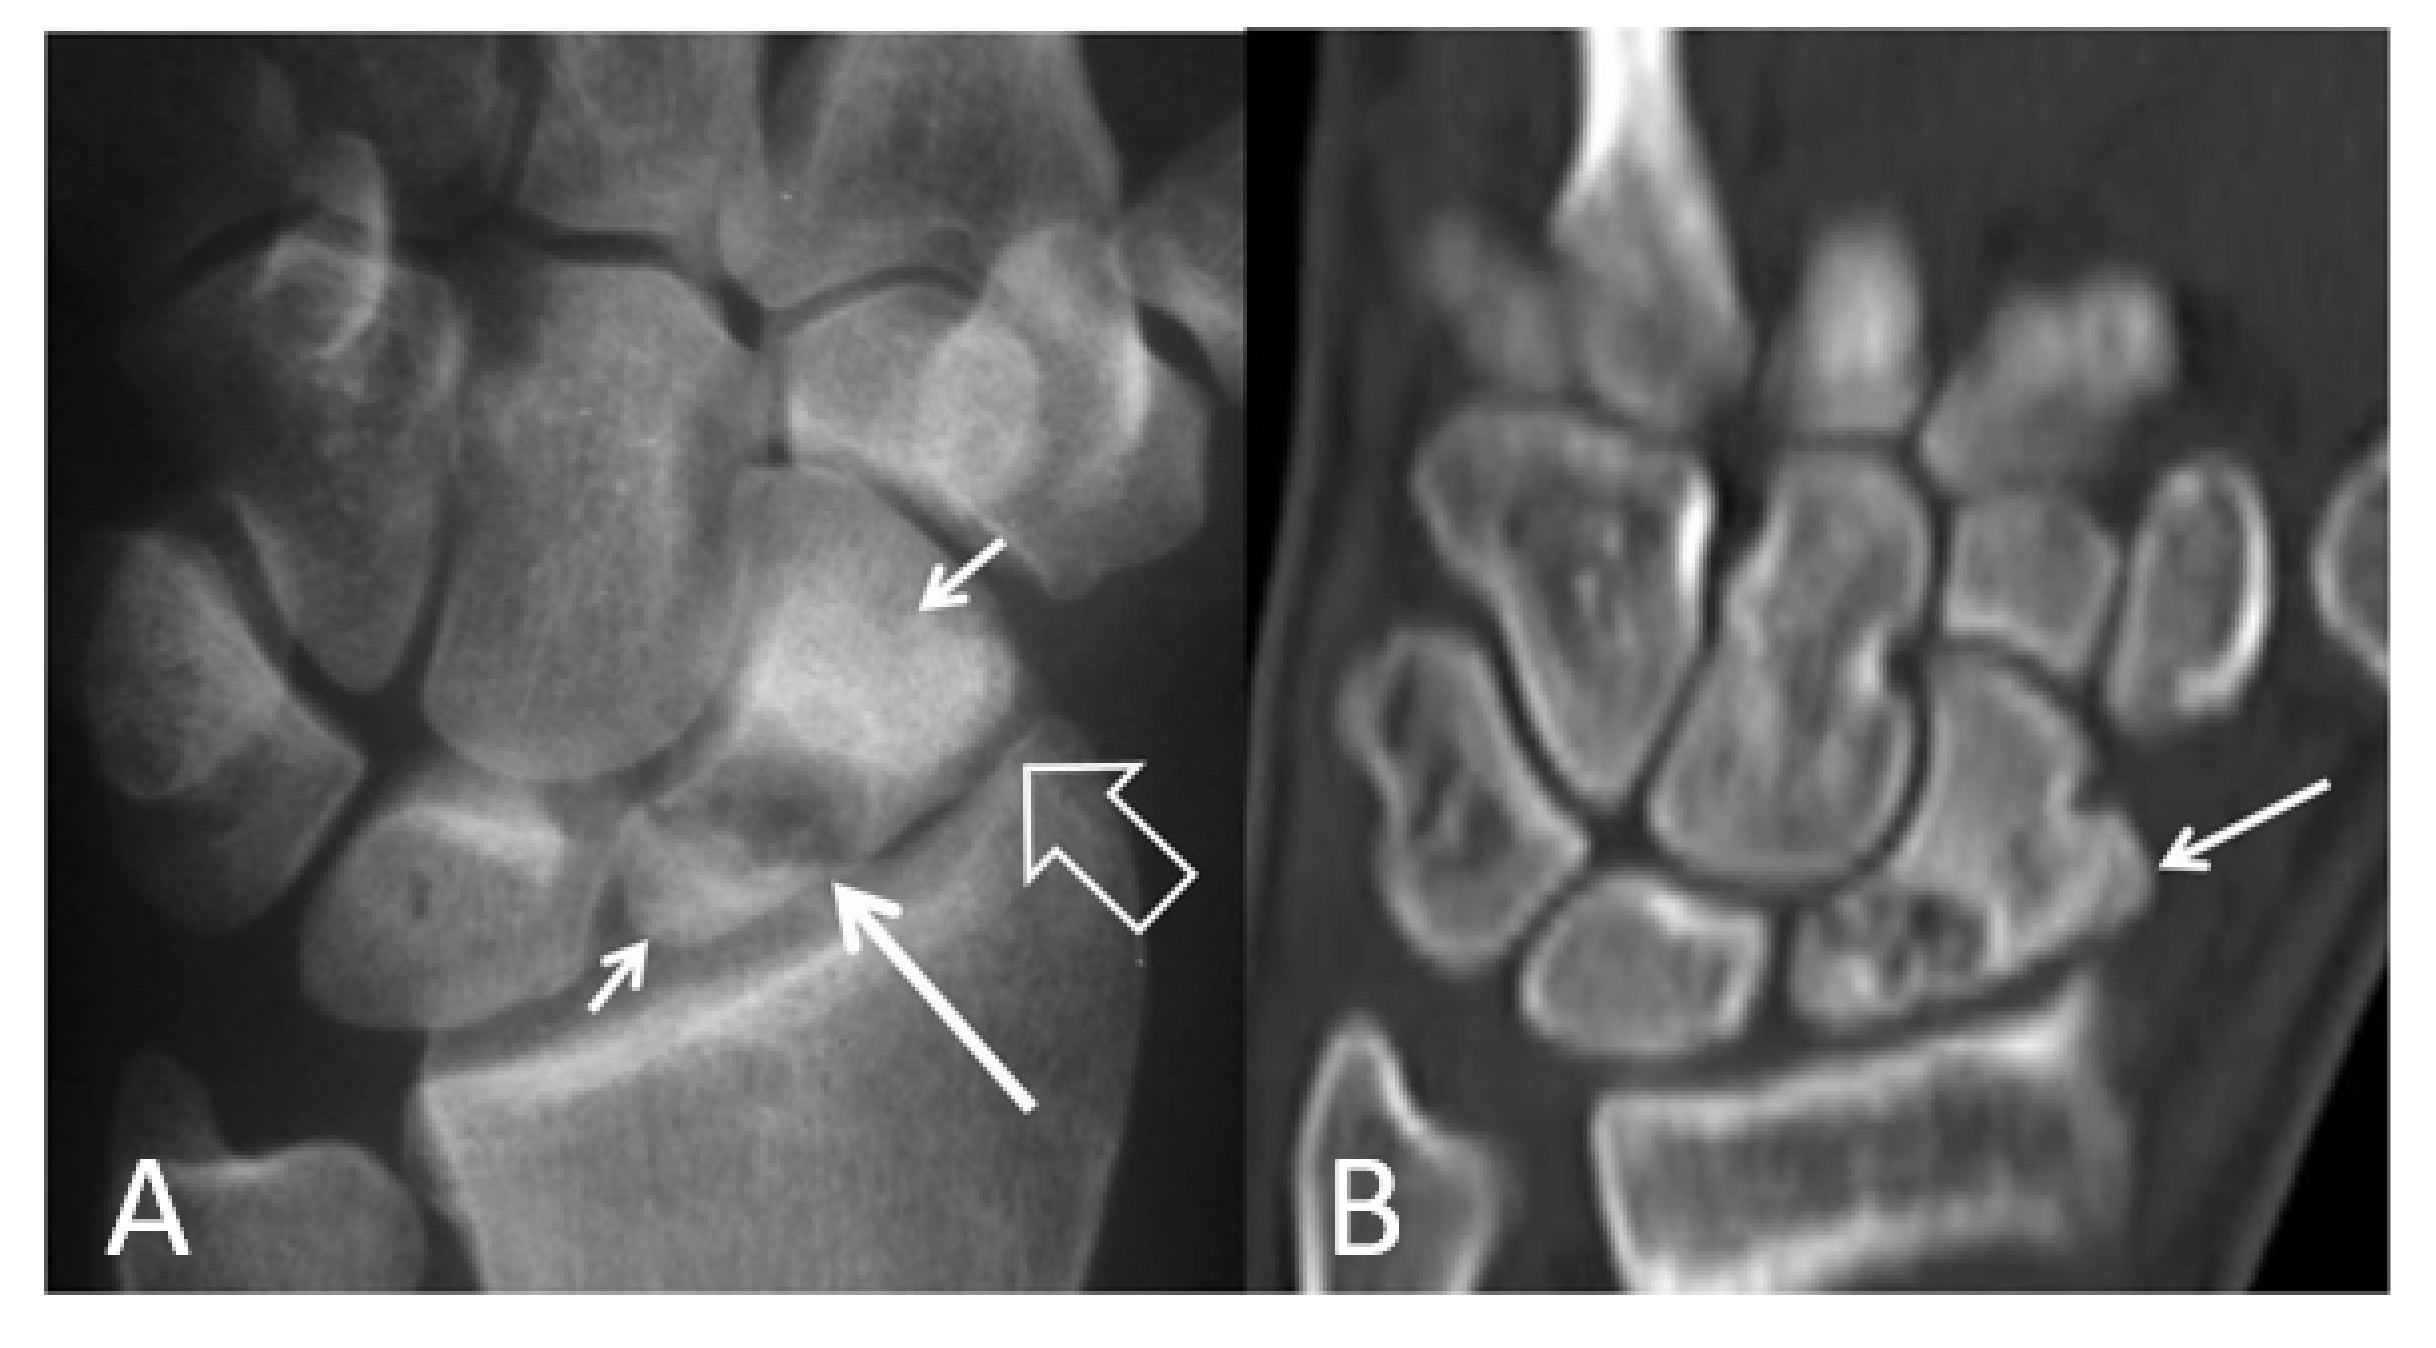

Figure 13.

A 41-year-old male patient with a scaphoid fracture 5 years prior to current imaging and persistent pain and functional impairment during the last 2 years. (A) PA radiograph showing proximal pole osteosclerosis in keeping with osteonecrosis (open arrow) and radial radioscaphoid joint space narrowing with minimal subchondral sclerosis in keeping with SNAC stage I disease (arrow). (B) Coronal T1w MR arthrographic image showing irregularity of the radioscaphoid space (arrowheads) and low signal intensity of the scaphoid bone marrow suggesting global osteonecrosis (arrows). Subchondral sclerosis suggesting early osteoarthritis is shown on both images in the proximal capitate (small arrows).